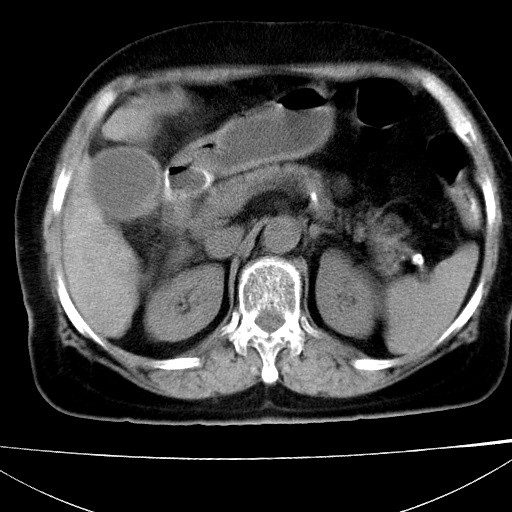

患者女74岁;右上腹胀痛1月,伴恶心,无发热;生活在疫水区。有术后病理及术后半年的追踪ct.

1)慢性血吸虫病(典型)。2)肝硬化。3)肝癌?4)胆囊炎。5)少量腹水。6)右侧少量胸腔积液。

支持.边缘见高密度线条样钙化影.

肝脏体积缩小,肝裂增宽,边缘不平呈波浪状,肝右叶见分隔状条索形钙化,亦见多结节低密度灶,边界不清,肝周可见少许液性暗区,胆囊增大内密度均匀,脾脏下缘低于脏脏的下缘,胸腔亦见液性暗区,余未见明显异常.

诊断:1肝硬化并慢性吸血虫病,脾肿大

2肝内占位,考虑肝癌可能性大,建议做增强

3胆囊炎, 4少量腹水及胸水

胆囊增大饱满,壁增厚。胆囊颈部见软组织密度影。临近肝右叶前段见片状低密度区,病灶下部见条状钙化,少量胸腹腔积液。意见:胆囊颈癌累及肝脏。

病人以胆囊癌手术的,病理结果为中分化腺癌。

现在看看肝右叶内圆形低密度影你们考虑什么呢?

肝内圆形低密度影考虑扩张的胆管

请看3mm重建像如下: